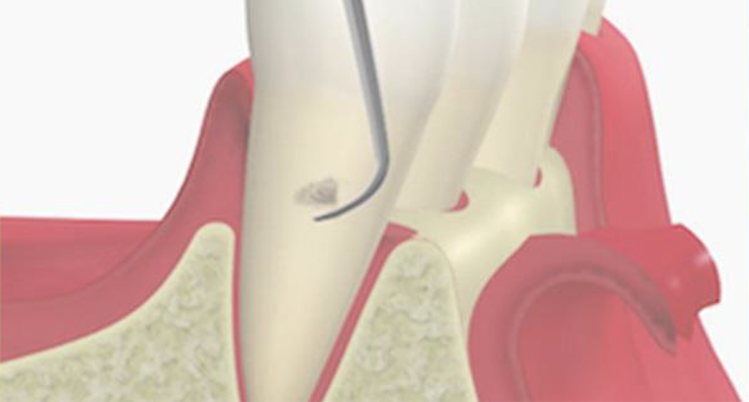

歯と歯茎の間の汚れをかき出すイメージイラスト

4. 歯周ポケット掻爬術

歯ぐきの内側の炎症をおこしている組織を取り除く処置です。

麻酔の効いている状態で行うため、治療中の痛みはほとんどありません。

内側からの炎症改善を目的としており、清潔になった歯の根に歯ぐきが付着し、汚れが溜まりにくい環境を作ることができます。

歯周ポケット掻爬術のイメージイラスト